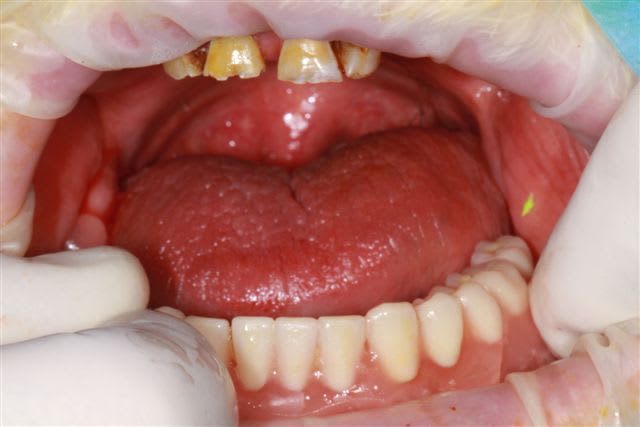

84 ans

sous anticoagulants

84 ans, il s'endormait littéralement en cours de chirurgie, toutes les peines du monde pour boucler le travail, je sais ce que j'ai vécu pour arriver à poser droit, alors les photos pendant la chirurgie... Je t'ai montré les deux prothèses successives, la première ayant été posée le soir de la chirurgie, je ne peux rien te dire d'autre. Alors tu peux rigoler tout ton saoul, cela ne me dérange pas le moins du monde... Ce que ta pano ne montre pas ce sont les expositions de spires sous gingivales, c'est là le noeud de l'affaire, mes implants n'ont pas de spires découvertes...